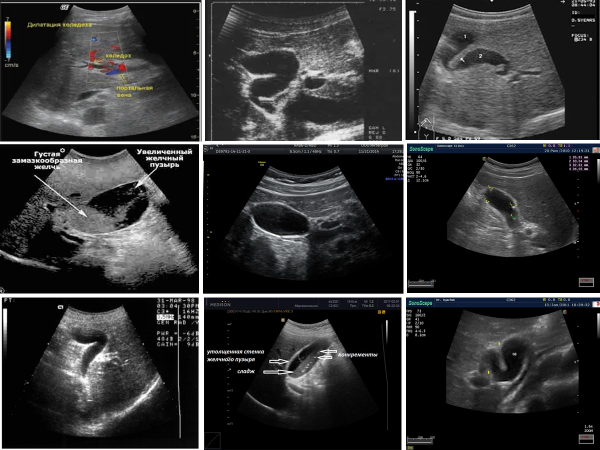

Функциональные нарушения желчевыводящей системы при УЗИ:

• Может быть увеличение размеров желчного пузыря при его гипотонии.

• Могут быть деформации и перегибы желчного пузыря.

• При дисфункции сфинктера Одди может быть небольшое расширение холедоха и/или панкреатического протока.

• Может быть эхогенный пристеночный осадок (сладж) или диффузная взвесь (мелкие эхогенные сигналы) в желчном пузыре – дифференцировать с ультразвуковыми артефактами!!!

• Может быть замазкообразная желчь в желчном пузыре или в желчных протоках – объемное изоэхогенное образование без акустической тени и без определяемой при ЦДК васкуляризации – дифференцировать

с опухолью!!!

• При вторичной дисфункции на фоне других заболеваний (постхолецистэктомический синдром, холелитиаз, холецистит, холангит, хронический панкреатит и др.) – соответствующая УЗ-картина.

• Основную роль в оценке моторно-эвакуаторной функции желчевыводящей системы играет холекинетическаяпроба с пищевой нагрузкой.